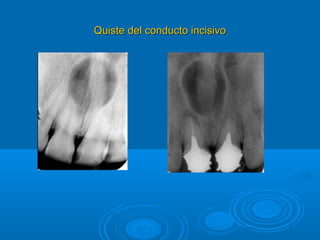

Quiste del conducto incisivo.-Quiste del conducto incisivo.-

Patogenia.-Patogenia.-

 Restos epiteliales del conducto incisivoRestos epiteliales del conducto incisivo

Presentación clínica.-Presentación clínica.-

 AsintomáticoAsintomático

 Puede manifestarse como tumoraciónPuede manifestarse como tumoración

 Puede haber dolor o creación de FístulasPuede haber dolor o creación de Fístulas

Radiología.-Radiología.-

 Imágenes Radiolúcidas en la línea mediaImágenes Radiolúcidas en la línea media

 Presenta una corticalPresenta una cortical

 Puede provocar divergencia de las raíces de I C Sup.Puede provocar divergencia de las raíces de I C Sup.

 Forma redondeado, oval, monolocular.Forma redondeado, oval, monolocular.

Quiste del conducto incisivoQuiste del conducto incisivo